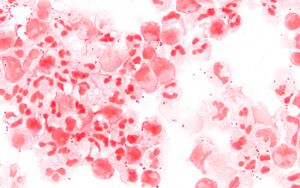

Scanning electron micrograph of a single N. meningitidis cell (colorized in blue) with its adhesive pili (colorized in yellow). The scale bar corresponds to 1 µm. | |